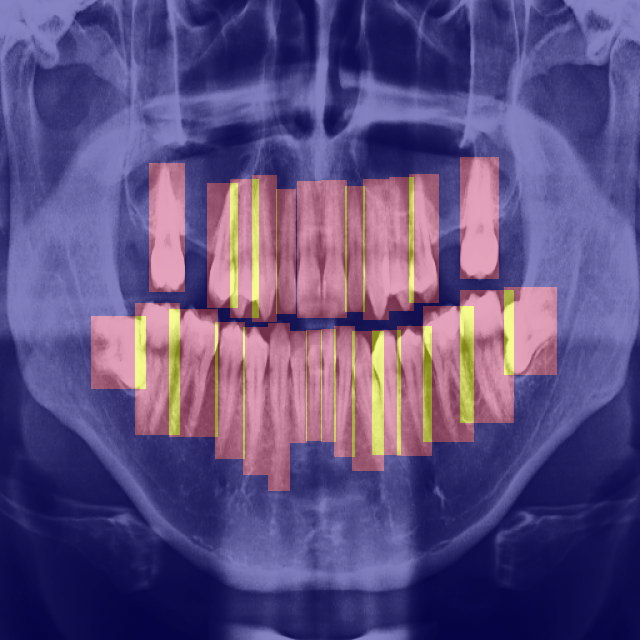

We propose a pipeline comprising a two-step process of YOLOv8 and BB-UNet architectures as shown in Fig.6. The first step involves training the YOLOv8 model to classify the teeth, locate the teeth, and extract the bounding boxes of each located tooth. The latter step is training the BB-UNet, for instance segmentation of teeth.

For training BB-UNet, the bounding box information from YOLOv8 was used to generate 512×512×3251251232512\times 512\times 32 bounding box binary maps which served as inputs to BB-Convolution layers. CLAHE [32](Contrast Limited Adaptive Histogram Equalisation) with a contrast limit of 0.02 was applied to enhance the details of the image. Horizontal and vertical flipping were used as data augmentation techniques, finally generating training data of 340 images and test data of 85 images. The model was trained with a batch size of 2 tensors of size 512×512×3551251235512\times 512\times 35, where 32 channels correspond to binary maps of bounding boxes and the remaining three channels correspond to the original image which served as inputs to the BB-UNet. Fig.8 shows the variation in training loss, validation loss, and dice coefficient on validation dataset over 60 epochs for BB-UNet training.

Comparatively, the BB-UNet segmentation method notably outperforms the standard U-Net segmentation regarding quality. Figure 12 highlights the superior pixel-level classification of teeth achieved by BB-UNet, especially in complex tooth structures like molars and premolars, where U-Net encounters challenges. Nonetheless, in scenarios where bounding box predictions are absent, as illustrated in Figure 13, BB-UNet’s performance aligns with U-Net due to the absence of prior knowledge.

The disparity in performance between models underscores the impact of dataset diversity on model proficiency, particularly in scenarios involving intricate tooth conditions like fillings, implants, or varying tooth degradation levels. Moreover, the dependence of BB-UNet’s performance on bounding box predictions emphasizes the importance of comprehensive data annotation for robust segmentation outcomes.

Refer to caption

(a) Panoramic X-Ray

(b) Ground Truth

(c) BB-UNet

(d) U-Net

Figure 12: Superior Segmentation results of BB-UNet over U-Net